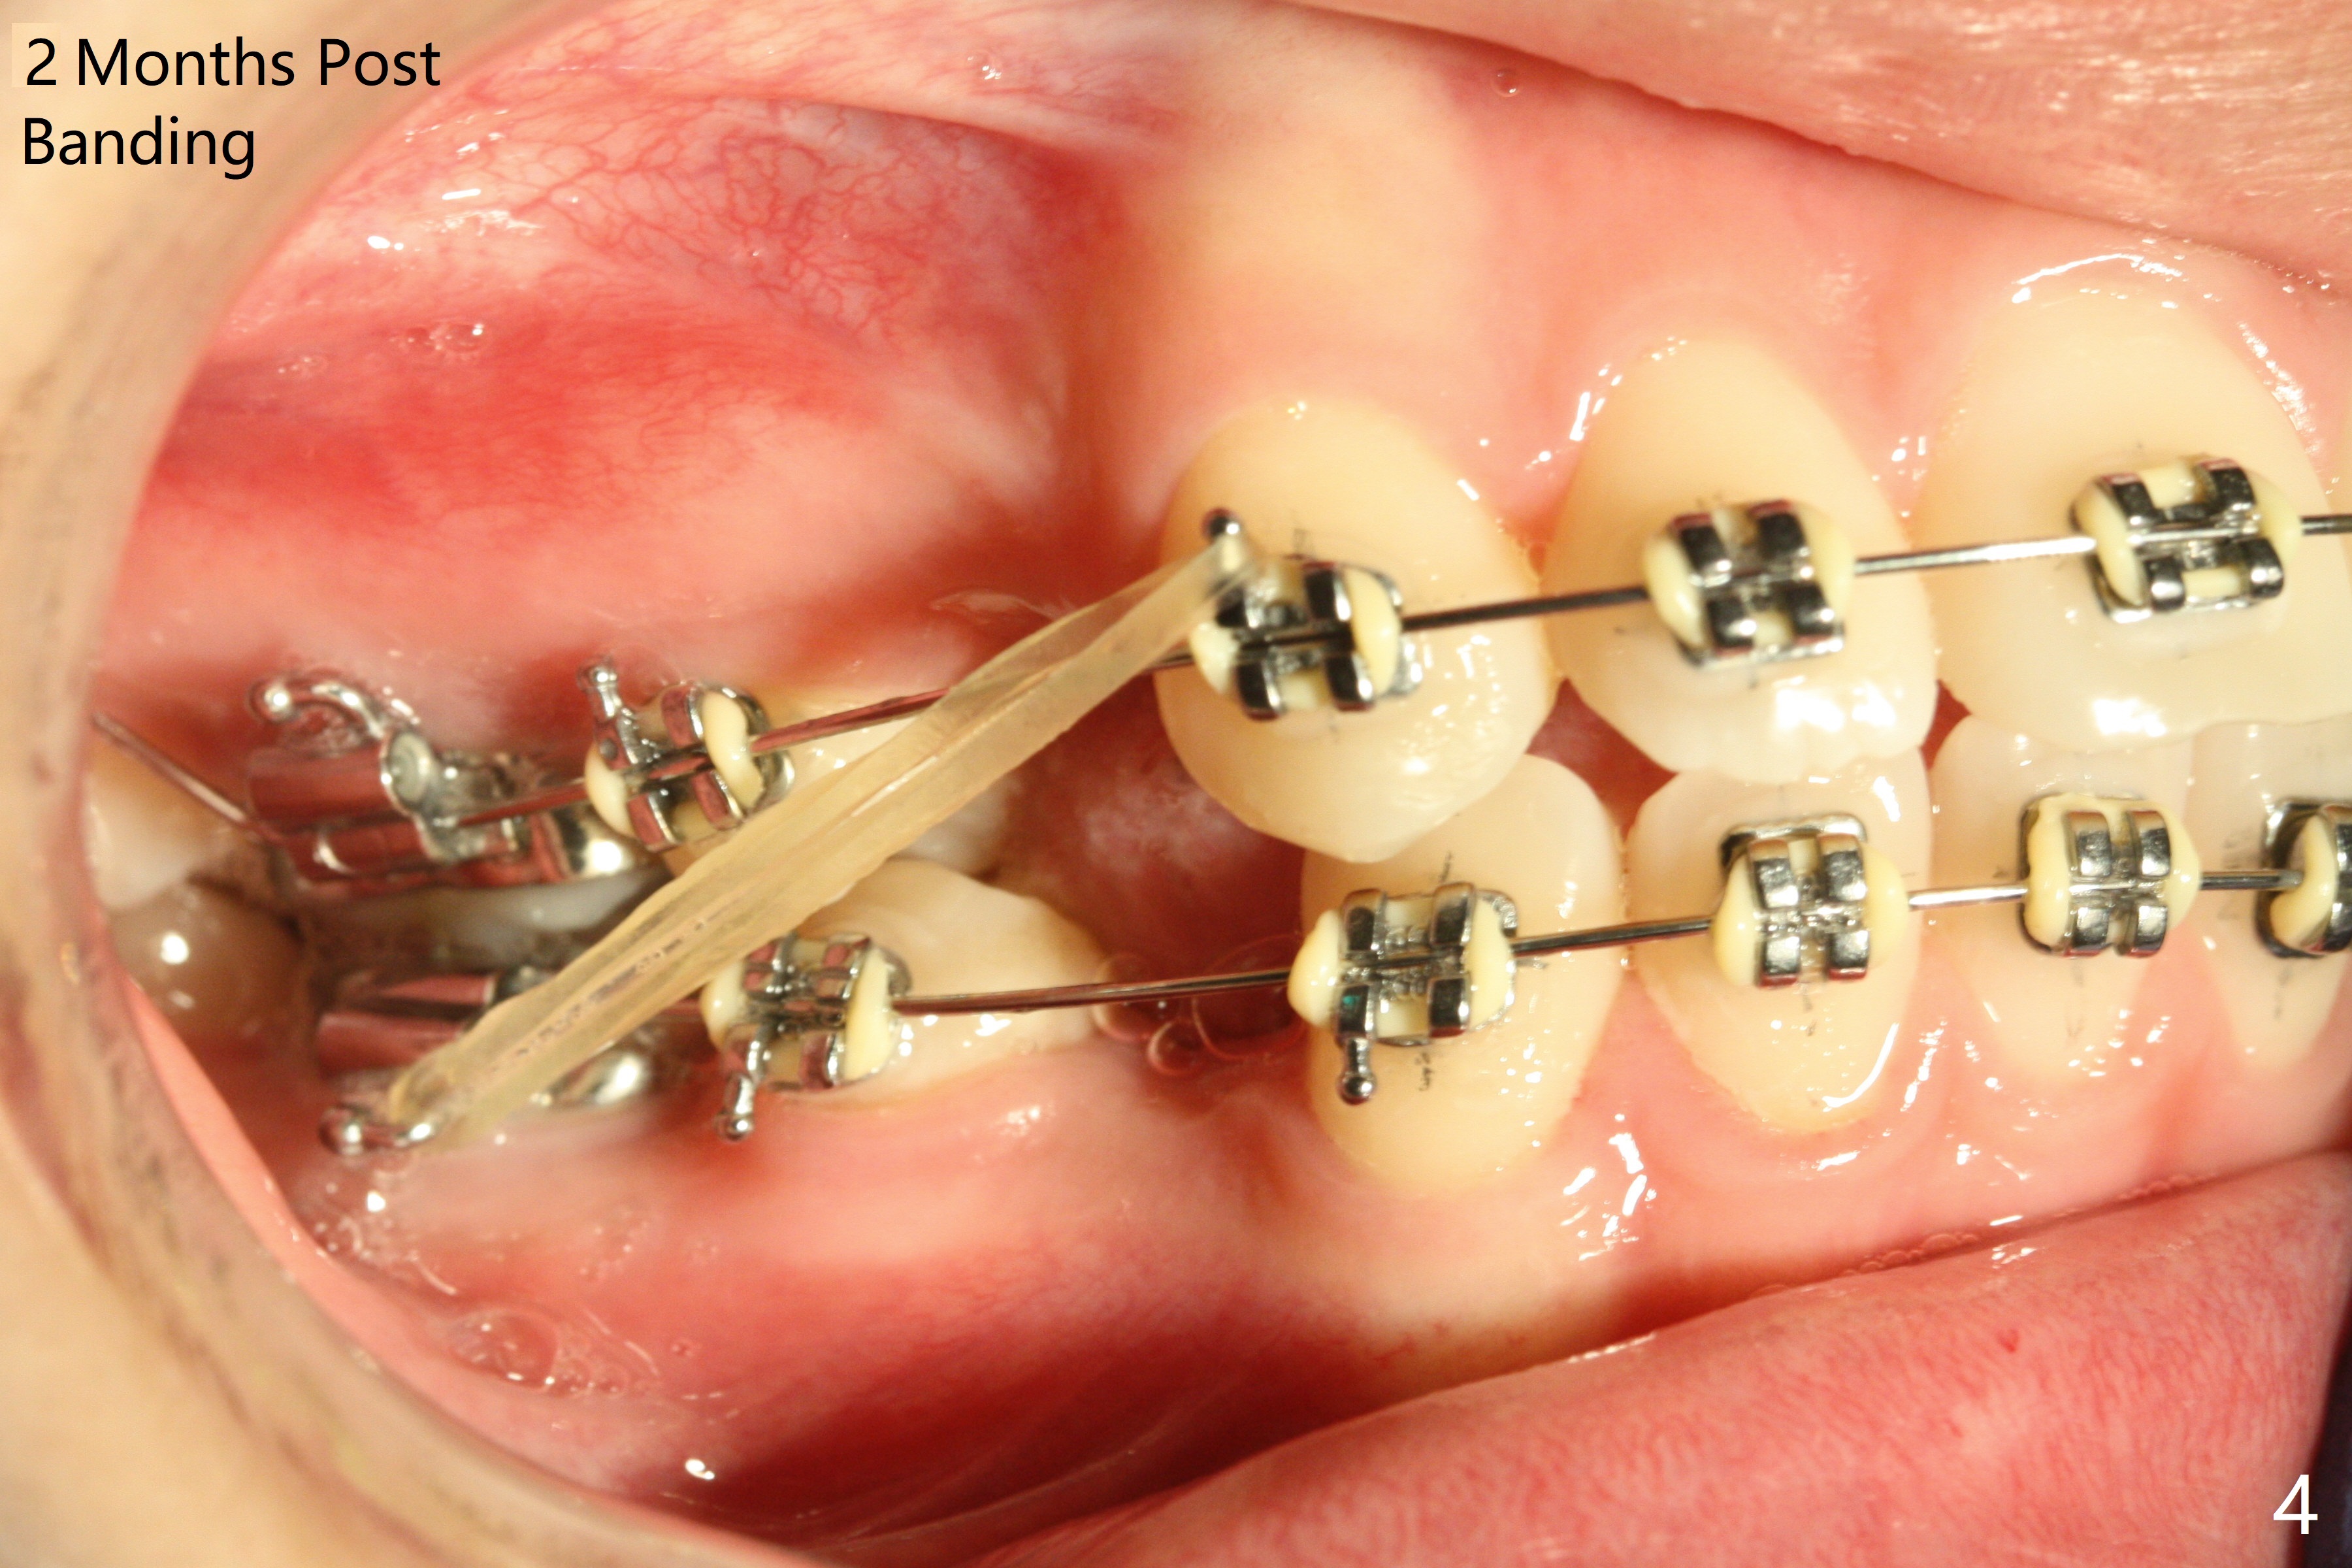

Two weeks post extraction of 4 bicuspids, brackets and bands are placed in 20 teeth (Fig.1-3, 14 niti). No bands are placed at 7s because of short crowns and tight contacts. When 16x16 wires are used, start Class II retraction. The latter is initiated with elastics when 18 ss wires are placed (Fig.4,5). U3s have been distalized with closed springs for 3 months (Fig.6,7). U2s are close to distalization 13 months post banding, 3.5 months post posted wire (Fig,8,9) with overjet (Fig.10). Class II retraction is re-initiated. When the upper incisors are retracted, the anterior overjet remains large. It appears that U6s have been retracted anterior, as indicated by the space between U6/7 (Fig.11), because of no use of U7s as anchors. Brackets are just placed with 18 niti arch wire. They will be retracted distal using the rest of the upper teeth and lower teeth (using Class II retraction) as anchor. There is root resorption of the upper anteriors 2 years 1 month post banding (Fig.12,13).